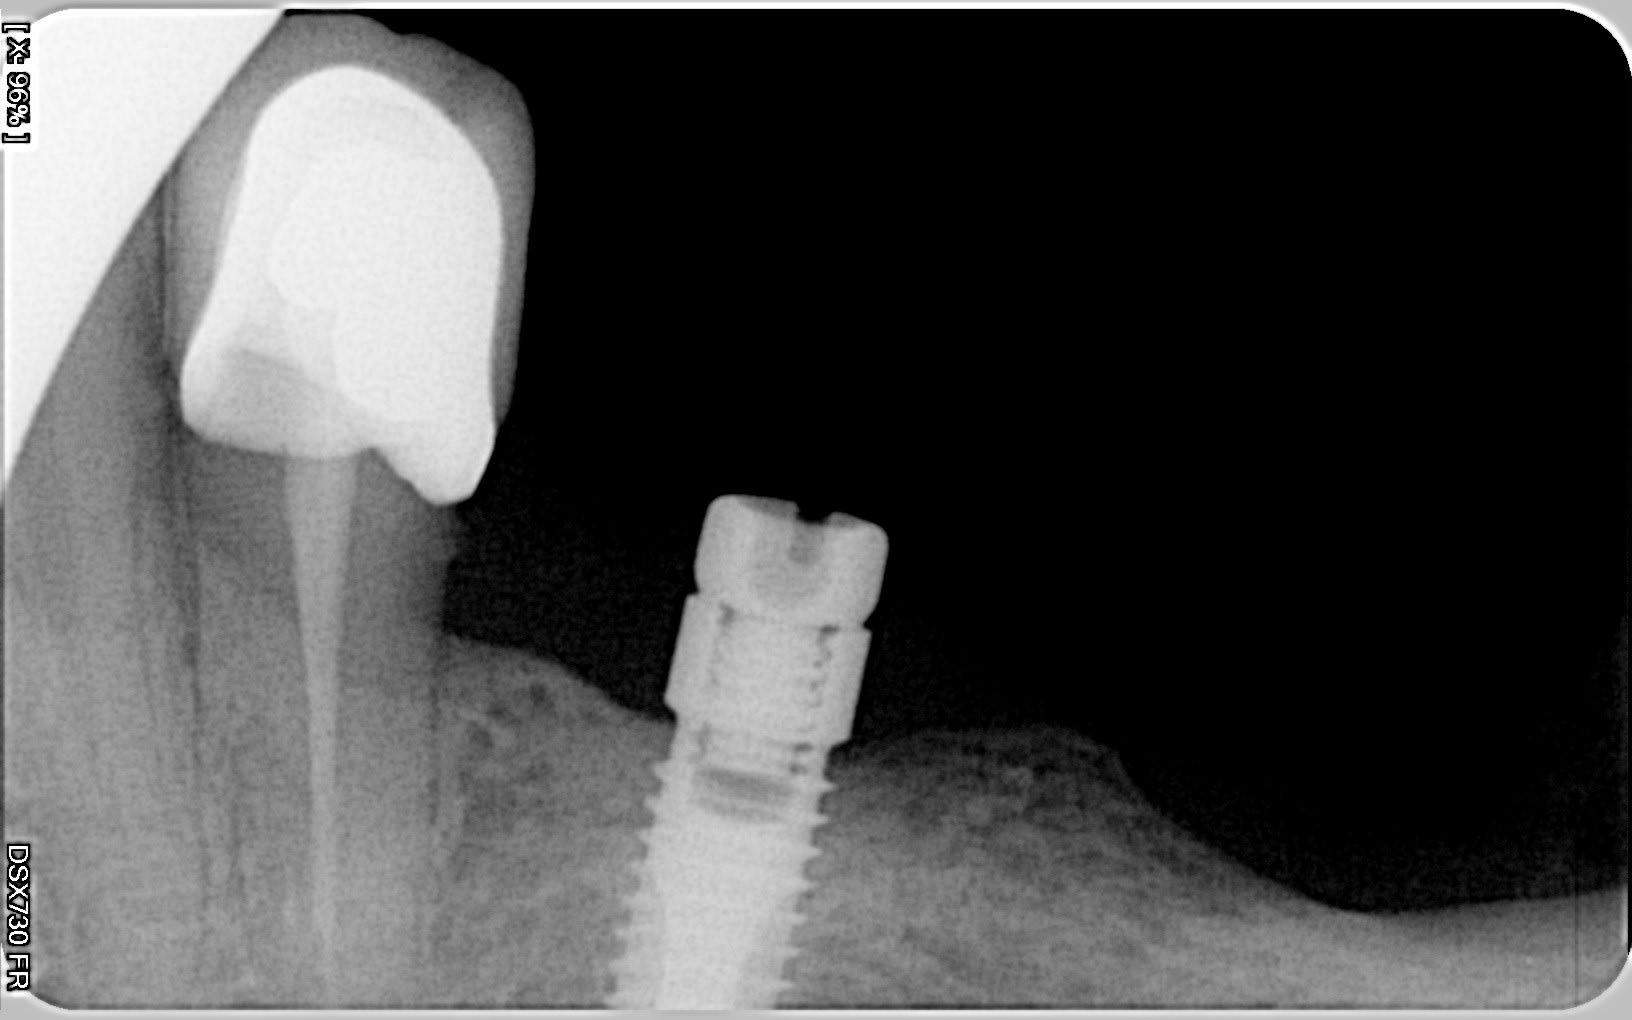

l'implant "lisse" impacté c'est un IMZ

l'autre avec les spires c'est un steri-oss (quasi sûr, dommage de ne pas avoir l'apex de cet implant...l'évent rond aurait permis un 100% fiabilité...)

ouaip, je confirme à 100% c'est bien du steri-oss...

pour les attachements...là???...je ne saurais pas te dire ce qu'il existe encore sur ces systèmes...qui ne sont plus commercialisés...

pour steri-oss, ceux qui avaient repris pour le suivi des pièces étaient Nobel... maintenant si ma mémoire est bonne Dentsply Friadent doit pouvoir avoir des pièces avec le système Atlantis...et comme de toutes façons tu auras à les contacter pour la gestion des IMZ (car c'est eux qui font le suivi d'IMZ), tu en profitera pour poser les (bonnes) questions...;-)